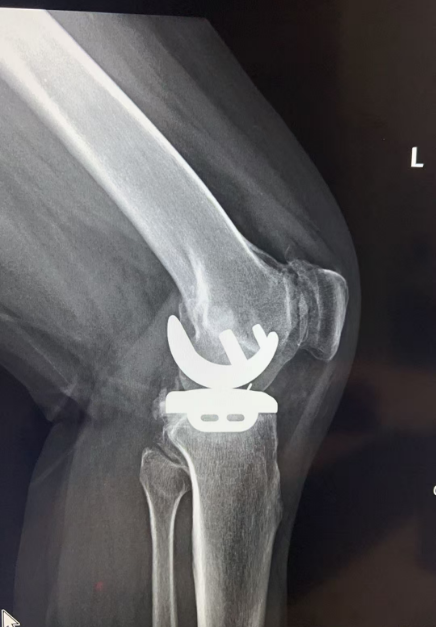

经过仔细评估,王歆峰主任决定给王阿婆做“左膝内侧单髁表面置换术”!这就是保膝治疗的一种,简单说,就是只修复膝盖磨损的那一部分,不用把整个膝盖关节换掉,创伤小、恢复快,还能保留膝盖原本的功能。

让王阿婆和家人都没想到的是,手术特别顺利,术后第二天,王阿婆就能下地慢慢行走了!王阿婆开心地说:“早知道有这么好的方法,我就不拖这么久了,之前连保膝是什么都不知道,还以为只能换膝盖,真是太感谢你了!”

什么是保膝治疗?

保膝治疗,就像是给磨损的膝盖“修修补补”,而不是“全盘替换”。它针对的是膝盖局部磨损的部位,保留膝盖其他健康的组织和功能。这样一来,手术创伤小,出血少,术后恢复也快,很多患者术后一两天就能下地行走,不用长时间卧床遭罪。